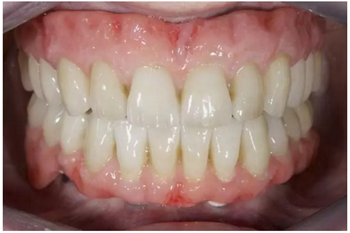

試戴上頜NobelProcera CAD/CAM海德式桿卡(IBO)以及下頜NobelProcera二氧化鋯種植橋(PIB)。

手術(shù)后16周最終修復(fù):上頜覆蓋義齒是卡扣在鈦桿卡(IBO)上,義齒牙冠部分是由二矽酸鋰玻璃陶瓷制作的單冠。下頜的氧化鋯種植長(zhǎng)橋(PIB)上同樣也制作二矽酸鋰玻璃陶瓷的單冠并進(jìn)行粘接。